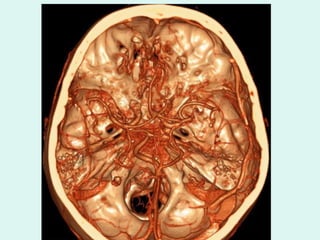

RECONSTRUÇÃO DE VOLUME

ANGIO CT INTRACRANIANA VERTEBRAIS

CEREBRAL MÉDIA ESQ. BASILAR VERTEBRAL ESQ . ANGIO CT INTRACRANIANA

ANGIO CT INTRACRANIANA BASILAR

ANGIO CT INTRACRANIANA BASILAR CEREBRAL POSTERIOR

ANGIO CT INTRACRANIANA CEREBRAL MÉDIA ESQ.

CEREBRAL MÉDIA ESQ.BASILAR VERTEBRAL ESQ . ANGIO CT INTRACRANIANA

ANGIO CT INTRACRANIANABASILAR CEREBRAL POSTERIOR

ANGIO CT INTRACRANIANACEREBRAL MÉDIA ESQ.